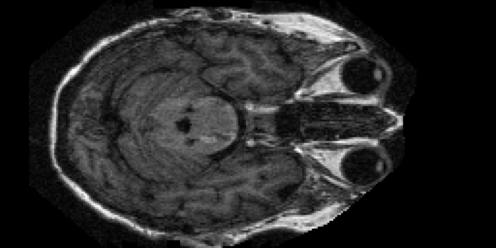

(a) Non-demented MRI sample.

Refer to caption

(b) Moderate dementia MRI sample.

(c) Mild dementia MRI sample.

(d) Very mild dementia MRI sample.

Figure 2: Representative brain MRI examples from the OASIS-1 dataset corresponding to the four Alzheimer’s disease categories considered in this study.